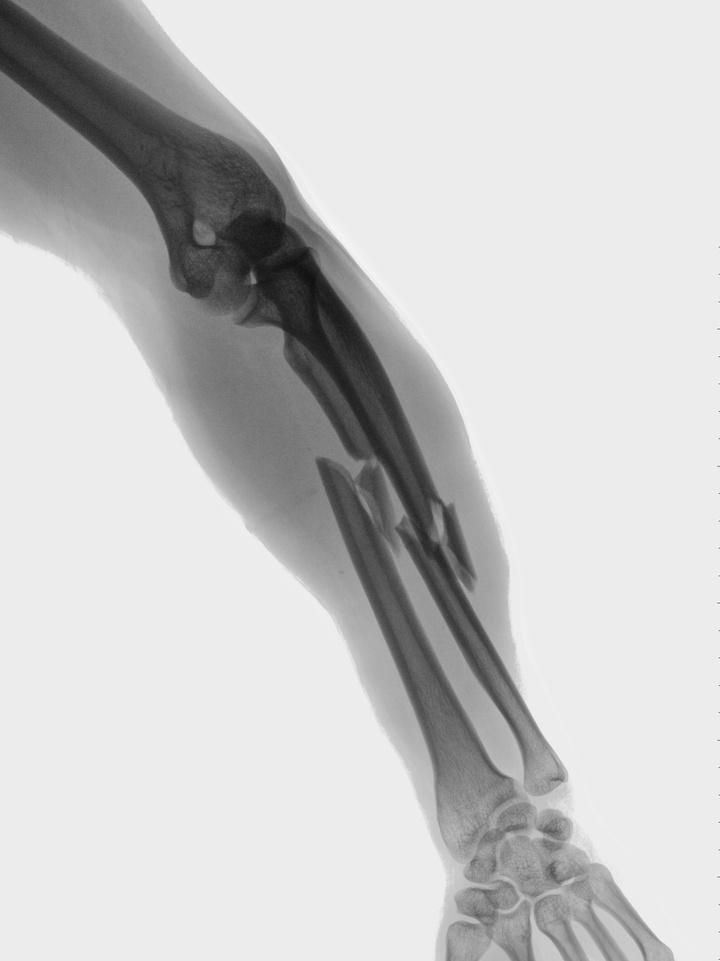

The way you find out you have osteoporosis is through a DXA scan (that’s Dual-energy X-ray absorptiometry). It’s a painless test, kind of like an xray but very low levels of radiation, and you lay down on the machine and the machine does a scan which tells you your bone mineral density… the actual mineral content in your bone…

And then it generates a score… and this score is called a T score.

And a T score is telling you how much your bone mass differs from the bone mass of an average healthy 30 year old adult.…

A score of 0 means your bone density is equal to the norm for a healthy young adult...

A score +1 and −1 is considered normal or healthy. A T-score between −1 and −2.5 indicates that you have low bone mass often times called osteopenia.

A T-score of −2.5 or lower indicates that you have osteoporosis. The greater the negative number, the more severe the osteoporosis.